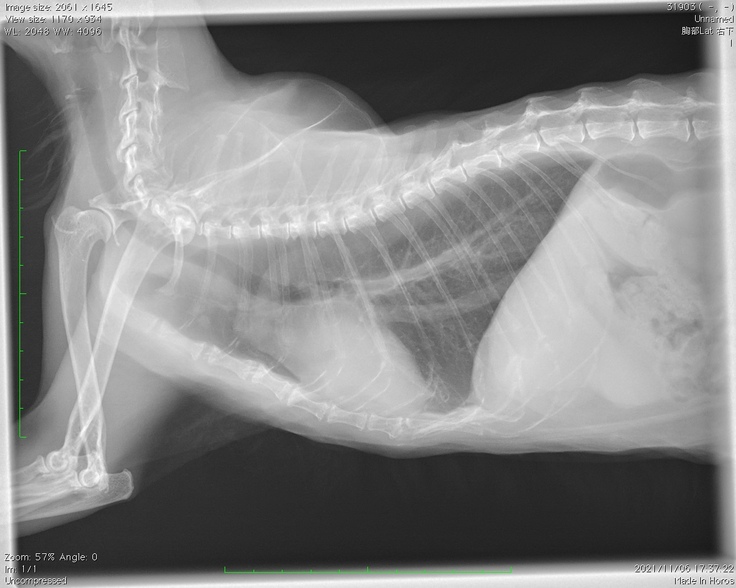

11月6日、予約しておいた腫瘍科のある動物病院にてセカンドオピニオンを受けてまいりました。

・レントゲンは撮影できるが、やはり麻酔なしでのCTやMRIは難しいということ。

・レントゲンの結果、上半身のリンパ節に転移が見られる。(ステージⅣレベル)

・肺にも薄い影があり、転移している可能性が高いとのこと。

上の画像は腸が炎症を起こしている様子だそうです。

下の画像は赤丸の中がほどんど腫瘍で『肉腫』の可能性もあるとのことでした。

レントゲン写真